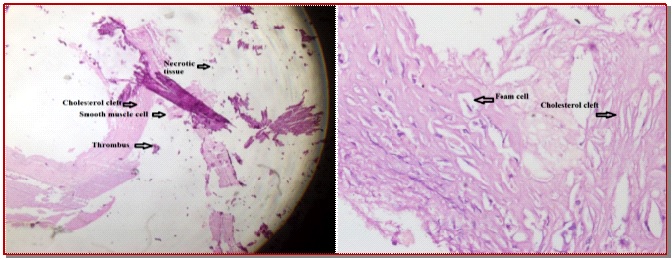

Histopathological analysis of the coronary atheroma extracted during coronary artery bypass graft surgery

This study aims to evaluate the histopathological analysis as well as the effect of coronary endarterectomy with severe calcified coronary artery disease. During the year of 2015 to 2017, a total of 135 patients (56 patients of stable angina and 79 patients of unstable angina) underwent atherectomy in adjunct to off-pump coronary artery bypass graft surgery. Histopathological study of atheroma specimen demonstrates the presence of calcification, foam cell, cholesterol clefts, thrombus, smooth muscle cell, and also necrotic tissue using standard hematoxylin and eosin stain techniques. However, smooth muscle cells and foam cell were identified with plaque using the monoclonal antibodies. Thrombus was more common in unstable angina group of patients (64.4%) in comparison to the patients with stable angina (23.2%). An accelerated progression pattern of smooth muscle cell proliferation and calcification were observed which was also common and significantly higher in unstable angina group of patients. The presence of thrombus and accelerated progressive pattern of smooth muscle cell proliferation in unstable angina patients imply the episodic disruption of atheromatous plaque followed by subsequent healing and may play a vital role in the pathophysiology of underlying angina pectoris.